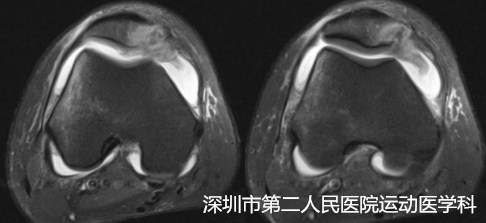

MRI下明显的软骨撞击征

核磁(MRI)往往能够确诊,表现为:内侧髌股韧带松弛、扭曲、高信号改变;髌骨内侧软骨损伤呈高信号改变;股骨髁外侧软骨受损;关节内水肿信号;而X光和CT有时无明显异常。